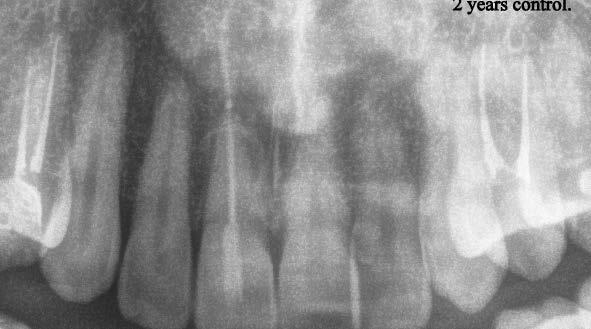

a-m. ábrák: Preoperatív röntgenfelvétel (a) és preoperatív CBCT-felvétel a jobb felső 5-ös (1.5) fogról, sagittalis (b) és axialis (c) nézetek. Az intraorális szkennelés során kapott STL-fájl (d). A 1.5-ös fog navigált endodonciai mikrosebészeti beavatkozásához tervezett sablon (e). A 1.5-ös fog navigált endodonciai mikrosebészeti beavatkozásához nyomtatott sablon (f). Teljes vastagságú mucoperiostealis lebenyt emeltünk (g). A sablont a helyére illesztettük, és a csontablak határait jelöltük (h). A fog gyökerén kívül eső, betört eszköz a 1.5-ös fog periapicalis régiójában (i). Az eltávolított betört eszköz (j). A rezekció, retrográd preparáció és a TotalFill BC RRM Fast Set Putty anyaggal elkészített retrográd gyökértömés utáni röntgenfelvétel (k). A lebenyt varratokkal rögzítettük (l). A kétéves kontroll során készített röntgenfelvétel (m).

gítségével tovább módosítottuk. Az így kapott sebészi sablon egyértelműen meghatározta a periapikális terület eléréséhez szükséges csontablak határait (2. e-f. ábra) Helyi érzéstelenítést követően teljes vastagságú mucoperiostealis lebenyt képeztünk, majd a buccalis csont feltárását követően (2. g. ábra) a sablon segítségével bejelöltük a preparálandó csontablak határait (2. h. ábra). A csontablak kialakítása során Piezotome CUBE LED kézi-darabot alkalmaztunk, majd a leemelését követően a betört eszközt megkerestük (2. i. ábra) és eltávolítottuk (2. j. ábra). A rezekciót ultrahangos megmunkáló fejekkel (ACTEON) végeztük, majd retrográd preparáció következett.

A retrográd gyökértömés elkészítése során TotalFill BC RRM Fast Set Putty-t (FKG) használtunk (2. k. ábra). A lebeny széleit 5/0-s Prolene varratokkal egyesítettük (2. l. ábra). A varratok a műtétet követően 72 órával kerültek eltávolításra. A beteg két évvel később kontrollröntgen készítése céljából érkezett rendelőnkbe. A vizsgálat során a fog tünetmentesnek és funkcióképesnek bizonyult (2. m. ábra).